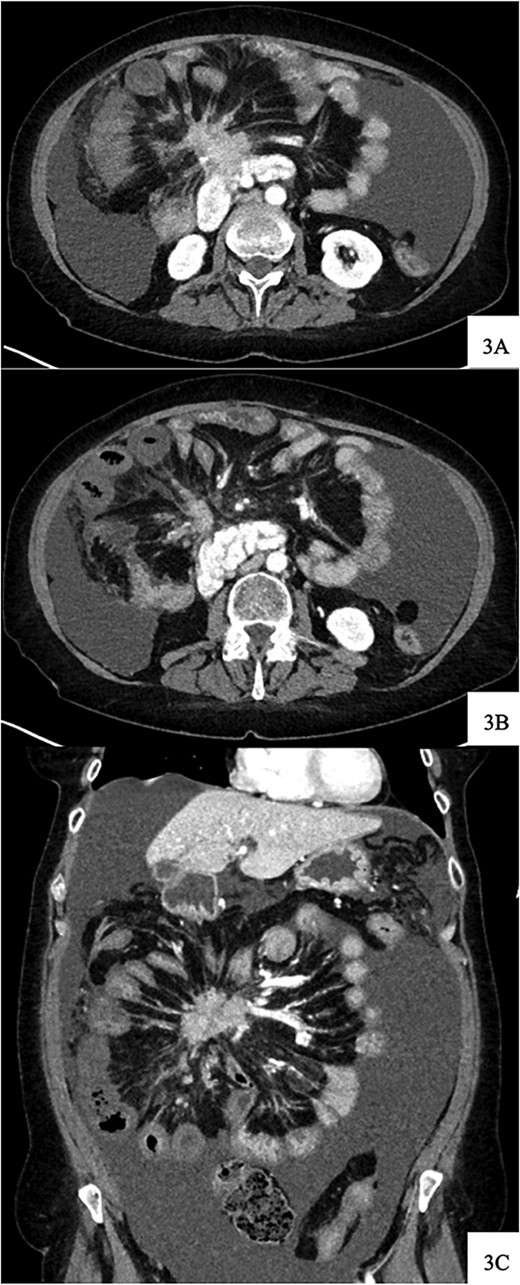

Upon arrival, she was afebrile with stable vital signs but appeared uncomfortable with significant abdominal pain. Her labs revealed leukocytosis, anemia, and absent lactic acidosis. CT demonstrated decreased enhancement and bowel wall thickening of several small bowel loops within the right lower quadrant, which were new compared to prior imaging (Fig. 4).

Contrast-enhanced axial CT image at time of presentation shows spiculated central mesenteric mass severe narrowing of the SMV with probably occlusion and encasement of the SMA with possible occlusion (A) associated with decreased enhancement and bowel wall thickening of several small bowel loops within the right lower quadrant (B). Coronal reformatting demonstrates the relationship of the mesenteric mass and affected small bowel (C).

Given her abrupt-onset abdominal pain in the setting of a tumor involvement of the SMA and imaging findings concerning for bowel ischemia, the decision was made to proceed with exploratory laparotomy after discussion regarding goals of care with the patient and her family.